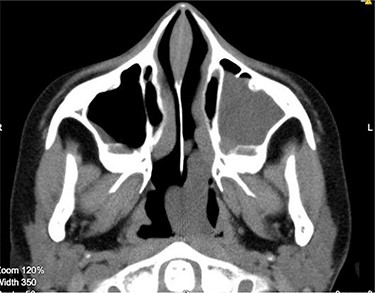

Anterior rhinoscopy revealed hypertrophied inferior turbinates with allergic nasal mucosa and increased nasal secretions with no mass seen. There was no active pus discharge from the nose. On throat examination, a large red, strawberry shaped mass was seen hanging posteriorly in the oropharynx. Flexible nasal endoscopy (FNE) of the left nostril was done, revealing a large polyp extending from the middle meatus into the choana and a clear right airway. A computerized tomography (CT) scan was done (Figs 1 and 2) showing a soft tissue mass arising from the left middle meatus, extending posteriorly and reaching the left choana (Fig. 2).

CT scan axial cut showing a large homogenous mass extending across the left nasal cavity.